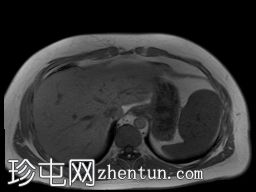

轴位T1加权像

同相位序列

T1低信号,T2低信号为主的脾脏肿块,内部可见T2高信号分隔,呈进行性强化。肿块中央可见星状瘢痕。

脾脏硬化性血管瘤样结节性转化(SANT),9.8 cm肿块

顾名思义,脾脏硬化性血管瘤样结节性转化(SANT)是一种纤维性血管病变。本病例展示了SANT的一些典型影像学特征,包括边界清晰的病灶,中央可见瘢痕,以及呈放射状进行性强化。这些特征使得术前MRI诊断较为明确。尽管SANT是一种良性病变,但大多数患者仍需行脾切除术以明确病理诊断。